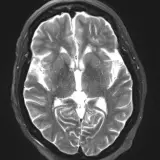

Neuro MRI